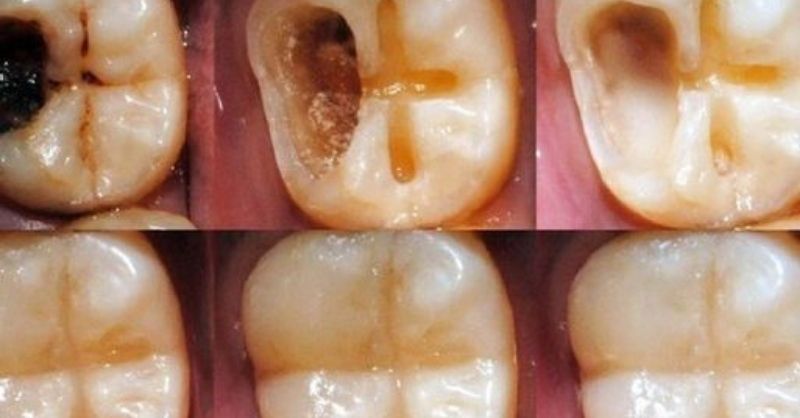

How to Naturally Repair a Cavity & Strengthen Your Teeth

Cavities develop when bacteria break down tooth enamel, leading to decay. While professional dental treatment is necessary for severe cavities, early-stage decay may be managed by strengthening enamel...